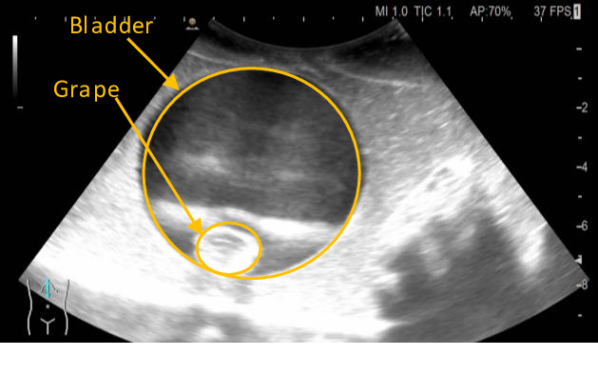

Refer to caption

Figure 12: A screenshot of the ultrasound scan shows a water bladder inside the grape.

The ultrasound scan experiment evaluates the ability of the system to perform a remote diagnostic test, which requires the design of an end-effector for holding the ultrasound probe (Fig. 4.c). However, the available ultrasound scan does not allow remote control, so the experimental setup has been modified. This experiment is performed in the line of sight teleoperation. However, the phantom was placed above the operator’s line of sight to hinder the perception and promote the use of the video feedback from the ultrasound scan. We use a phantom made of commercial food gelatin mixed with psyllium husk to enhance the contrast. We have three layers of gelatin with different water components; the first has the recommended water to gelatin ratio. In the second layer, the amount of water is halved, and on the top layer, the water is reduced to one third. Multiple props are suspended in the mix. There are bladders made of water balloons with grape inside to mimic masses, and some fruit (grapes) is also distributed outside the bladder directly in the gelatine. It is worth noting that we have used a high-frequency probe that is not ideal for the quality of the image. However, it does not make any difference in evaluating the physical interaction stability and dexterity, which are objectives for this experiment.

Fig. 11 shows the evolution of the interaction forces, the user input (𝒙dsubscript𝒙𝑑\bm{x}_{d}) and the stiffness of the replica arm, showing how the proposed method can dynamically adjust its stiffness to interact with the nonlinear environmental dynamics. The video also allows us better to appreciate how, once the contact is made with the phantom, the exploration can be driven mainly relying on the ultrasound monitor shown in 12. The main limitation in this experiment was that the available ultrasound did not allow remotely adjusting the image; thus, it requires being physically close to the patient.